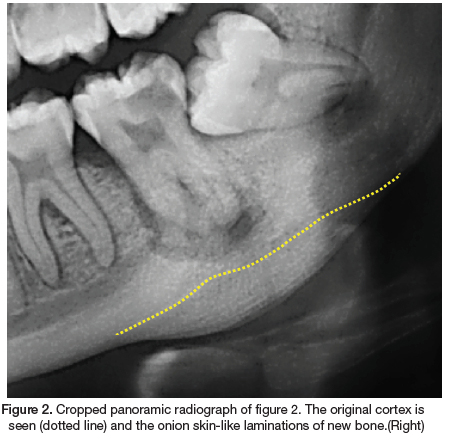

A 22-year-old female presented to our clinic with the main complaint of pain and swelling in the left mandible. The medical history revealed no co-morbidities. Extraoral examination revealed a draining sinus and a hard, firm swelling in the posterior left mandible. Intraoral examination revealed multiple carious teeth and healthy overlying mucosa. A panoramic radiograph was performed (Figure 1). Radiographic examination revealed a missing 18, impacted 28, 38, 48 and carious lesions on the 17, 15, 37 and 36. A periapical radiolucency is associated with the grossly carious 37 and in addition a convex radiopacity and onion skin-like periosteal reaction is noted, whereby numerous layers of new cortical bone is deposited in relation to the 37. The radiopacity extent includes the 37 area, with the affected bone appearing more sclerotic and dense. The adjacent cortical bone is normal. The periosteal reaction resulted in expansion of the cortical border, whilst remaining intact. There is a clear demarcation of the original cortical border and the new bone deposition (Figure 2). As the clinical and radiographic features were consistent with that of focal osteomyelitis with proliferative periostitis, a definitive diagnosis was made without the need for histological investigations. Subsequently, the grossly carious 37 was extracted and antibiotics was prescribed. The patient responded well to the treatment and treatment of the other carious lesions has commenced.

Histologically, the affected bone forms multiple layers of bone in a parallel fashion, with an intact cortex. Radiographically, a convex radiopaque area is seen in the affected area, with parallel layers in relation to the source of infection. Depending on the radiographic angulation, occasionally radiolucent layers can be seen as a soft tissue zone between the bony laminations and the original cortex. This radiographic appearance is often referred to as "onion skin".3